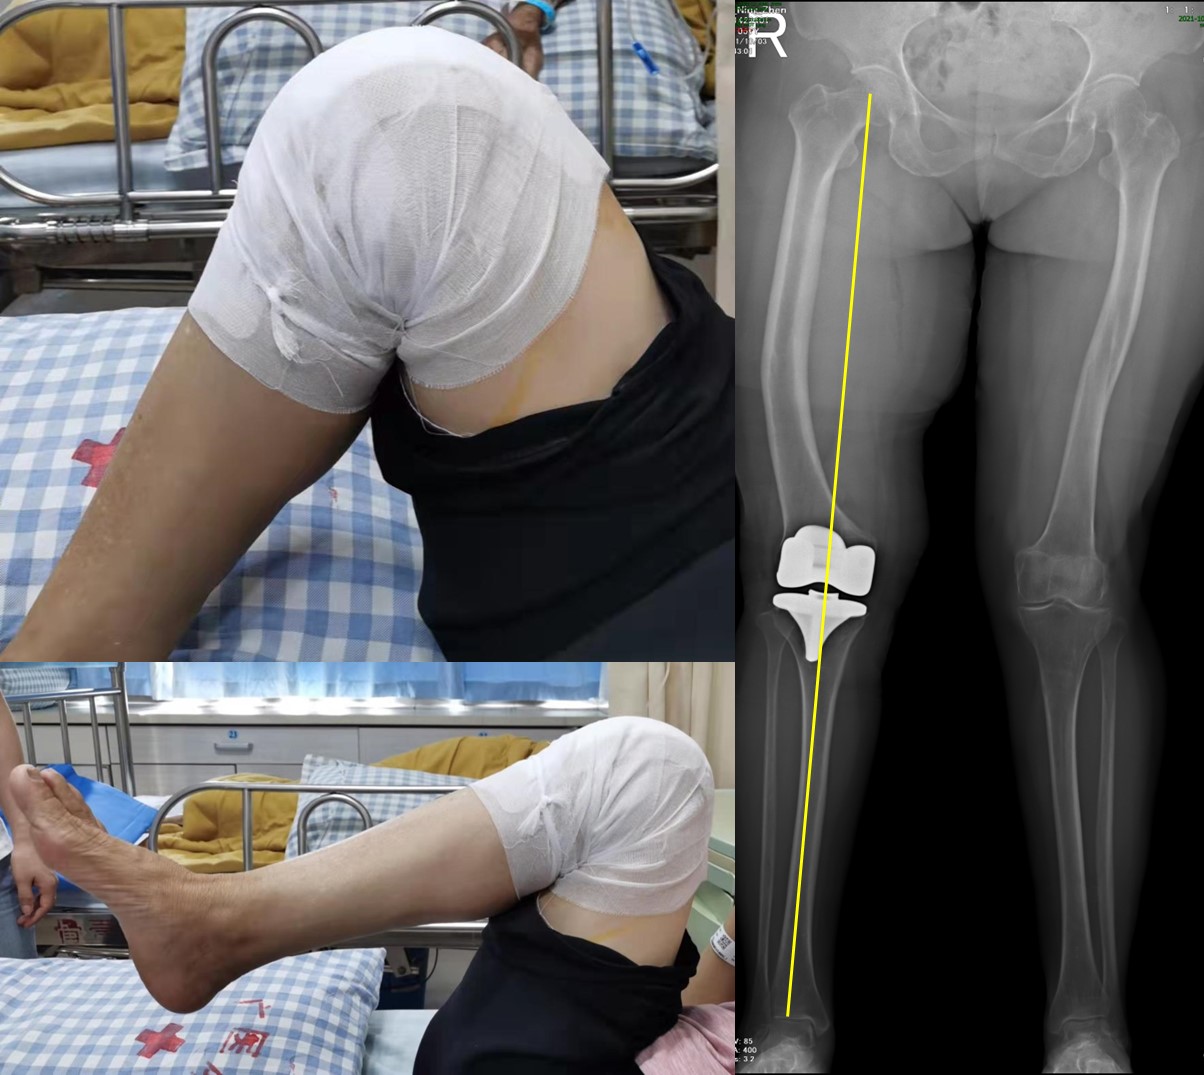

患者陆阿姨在儿时曾从高处摔下导致双侧股骨干骨折,经保守治疗获得畸形愈合,但直至骨骼发育的终止,患者双侧股骨畸形并未得到自然矫正,尤其是右侧股骨中段残留了约20°的内翻畸形。在长期下肢畸形和异常受力环境作用下,患者的右膝关节早早便发展至重度骨性关节炎(图1)。近6年以来,陆阿姨的右膝疼痛日益加重,辗转多方求医,得到的答复多是手术难度过大且需要先一期手术截骨矫正后再二期行关节置换术,然而该方案的风险和费用是她难以承受的。

图1 :术前查体及影像学评估